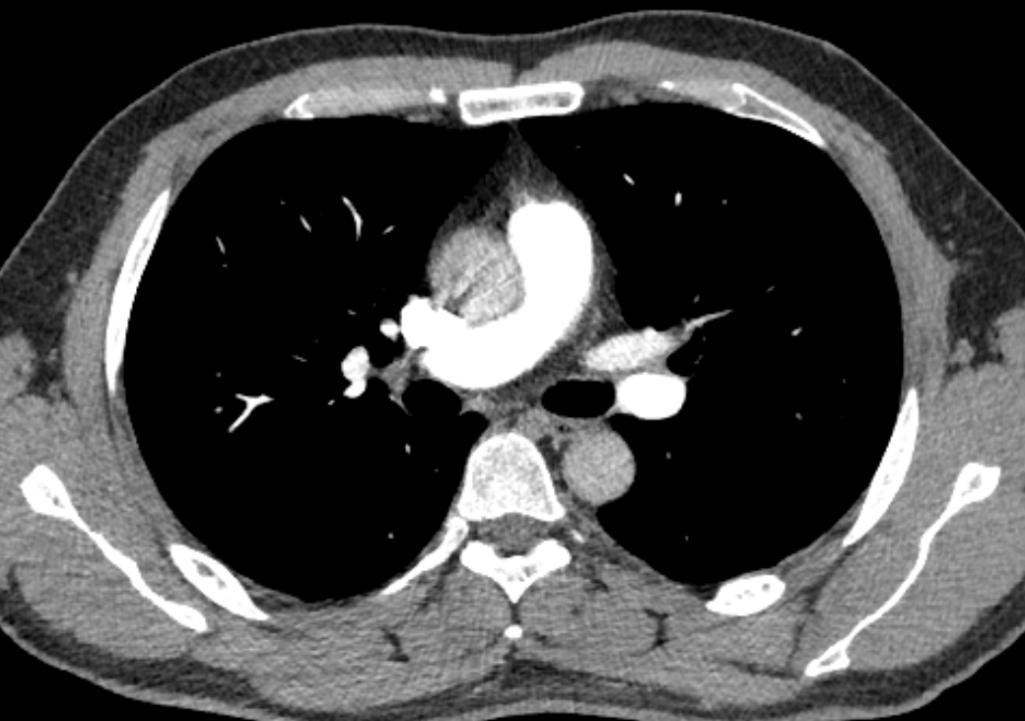

2)左上肢留置针穿刺高速团注对比剂时,不但行程远、还受主动脉弓压迫导致进入右心房的时间延长,同等体重患者需增加注射压力和药量。

进入肺循环的造影剂总量不足导致监测层CT值曲线迟迟达不到触发值

3)左头臂静脉回流产生线束硬化伪影,影响心脏及大血管造影检查。